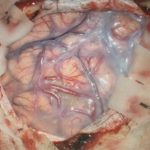

手術写真

手術前

手術中

手術後